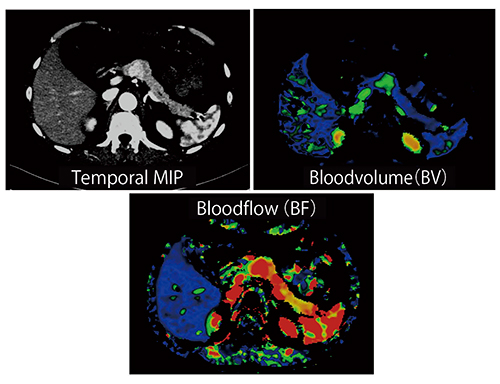

さらに,SOMATOM Forceでは心臓全体をカバーした心筋Dynamic Perfusionが簡便に可能なほか,MRIよりも優れている点として,特に冠動脈三枝病変の診断に重要な定量評価が可能なアプリケーションを有していることが挙げられる(図17)。

図17 心筋CT Perfusionの定量評価